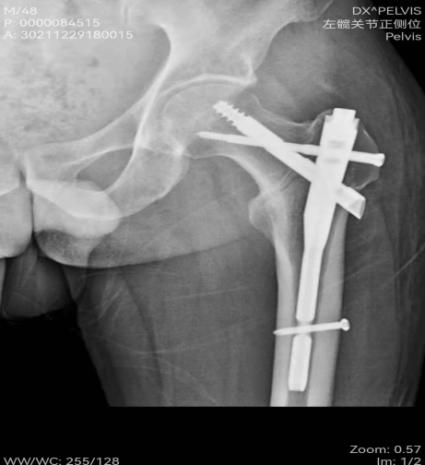

患者,48岁,有脑梗死后遗症且左侧肢体偏瘫,在家走路时不慎摔倒致左髋关节疼痛、活动受限入院。入院后查左侧髋关节X线片示:左股骨粗隆间骨折。骨外一科医疗团队在孙波主任主持下行病例讨论,并制定手术方案,决定行左股骨粗隆间骨折闭合复位内固定术(PFBN)。

通过医护加强多模式镇痛及快速康复技术,术后第2天,患者即可下地站立,在医护人员的帮助下,患者下地部分负重行走;术后13天顺利出院,患者及家属对医护人员表示由衷的感谢。术后复查X线片:骨折对位及内固定位置良好。